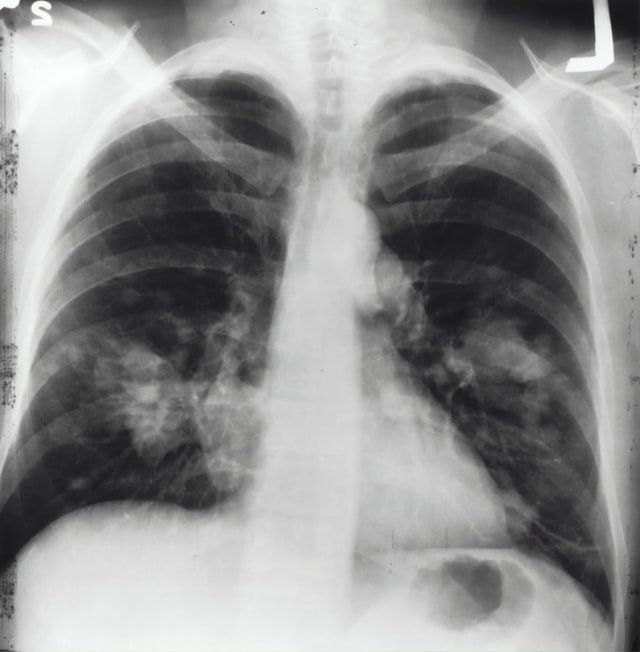

An estimated 10.6 million people fell ill with tuberculosis (TB) in 2021, an increase of 4.5% from 2020, and 1.6 million people died from TB (including 187 000 among HIV positive people), according to the World Health Organization’s (WHO) 2022 Global TB report. Continued challenges with providing and accessing essential TB services have meant that many people with TB were not diagnosed and treated. The reported number of people newly diagnosed with TB fell from 7.1 million in 2019 to 5.8 million in 2020. Reductions in the reported number of people diagnosed with TB suggest that the number of people with undiagnosed and untreated TB has grown. Learn more from WHO here.